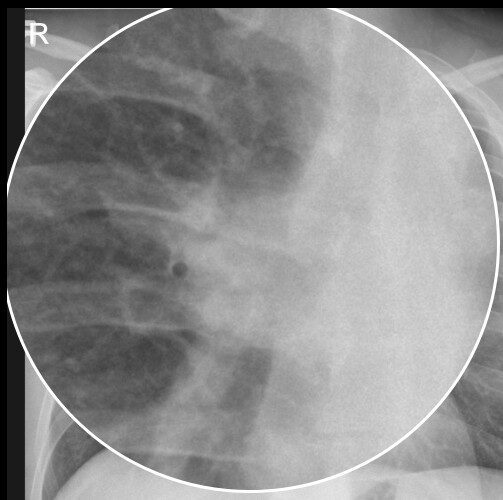

Pathologien des Lungenhilus

Eine sorgfältige Analyse des Lungenhilus ist essenziell, da viele pulmonale und kardiale Erkrankungen in diesem Bereich radiologisch erkennbar werden. Hier […]